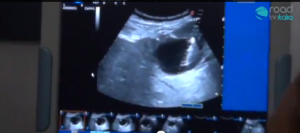

Grazie ad un gruppo di medici del SUN il 22 Settembre a Napoli in Piazza Dante si terra’ l’evento ‘A Napoli ci vuole fegato’, che ospiterà un team di medici e specializzandi che offriranno, gratuitamente, tutta la loro conoscenza e competenza medica, oltre ad uno stand attrezzato, per effettuare gratuitamente Ecografie epatiche a chi vorrà sottoporsi all’esame.

Ai microfoni di Roadtv Italia i Professori della SUN dell’Unita’ Operativa di Epatologia, Gastroenterolgia ed Endoscopia Digestiva, ci forniscono una dettagliata lezione, dove, utilizzando parole comprensibili per chi non ha studiato Medicina, ci parlano di come tutelarci da Epatiti, Fegato grasso, danni da Alcool e malattie oncologiche.